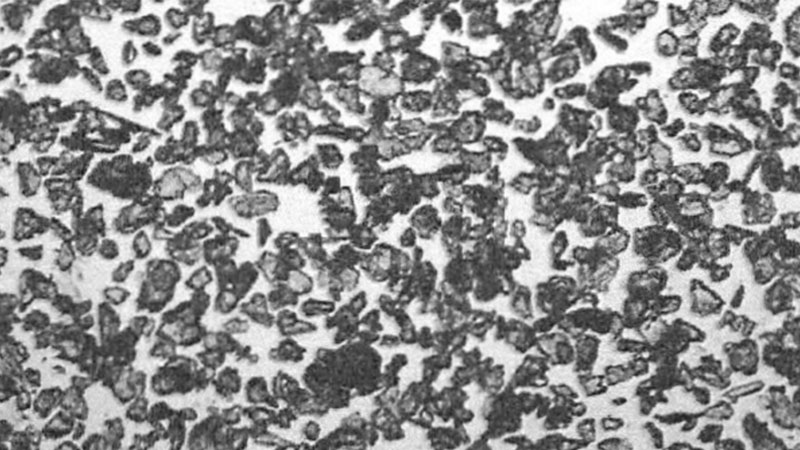

Poudrage avec STERITALC PF3